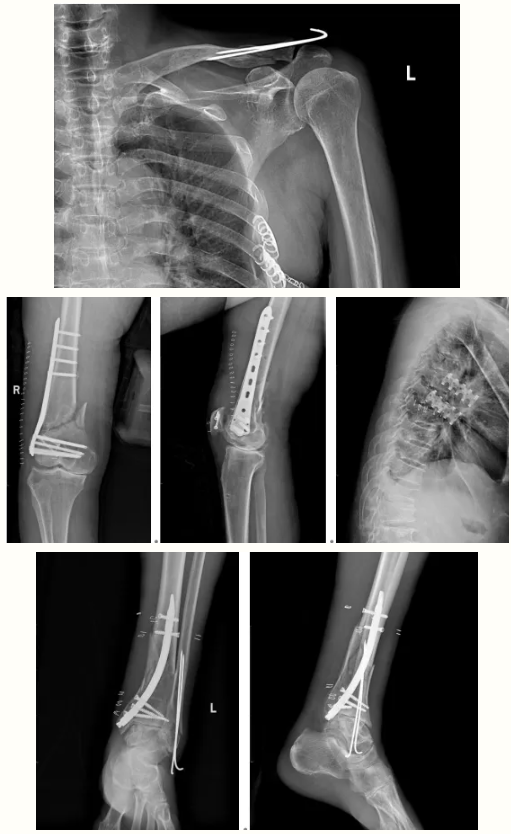

术前影像:

术后影像: